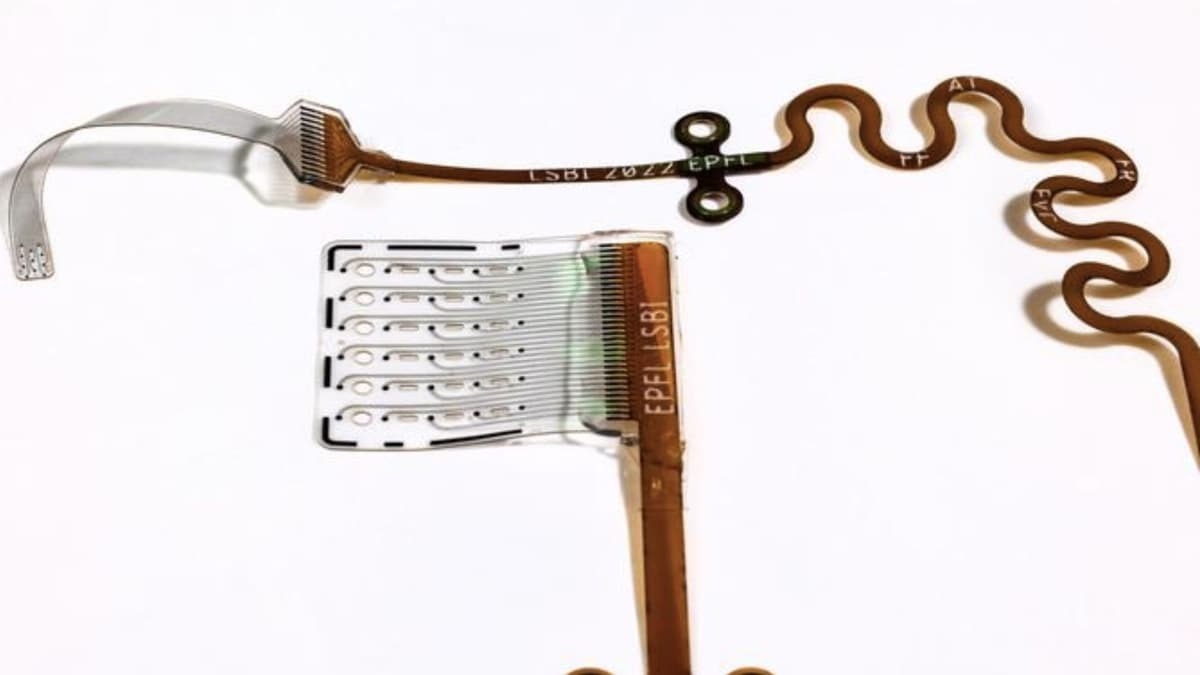

برنا - گروه علمی و فناوری: پژوهشگران با کارگذاری ایمپلنت های نرم در جنین قورباغه، موفق به ثبت زندهی رشد مغز از ابتدا تا بلوغ شدند.

برنا - گروه علمی و فناوری: محققان موفق به ساخت یک ایمپلنت انعطافپذیر جدید شدهاند که میتواند سطح شنوایی را در افراد مبتلا به کمشنوایی افزایش دهد.